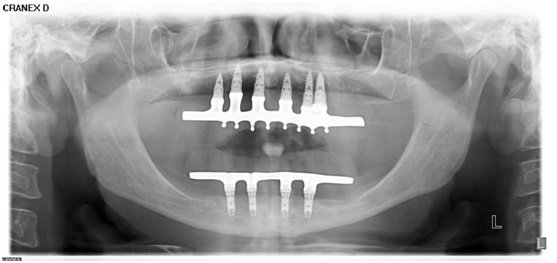

Após avaliação clinica acompanhada de exames de sangue complementares, foi pedido uma radiografia panorâmica e tomografia computadorizada do maxilar superior. Foi diagnosticada uma grande atrofia da maxila, evidenciando uma reabsorção óssea acentuada em altura e espessura.

Após conversar e analisar as opções de tratamento, optou-se pelo uso do rhBMP-2 (Infuse Bone Graft, 5,6 cc, Medtronic Sofamor Danek USA, Inc), associado ao beta tricálcio fosfato (Bone Ceramic, partículas 500- 1.000 micrometros, Straumann, Basel, Suíça) e telas de titanio (Titanium Augmentation Micro Mesh – 120 x 60mm e parafusos,Ace Surgical Supply Co.,Inc)